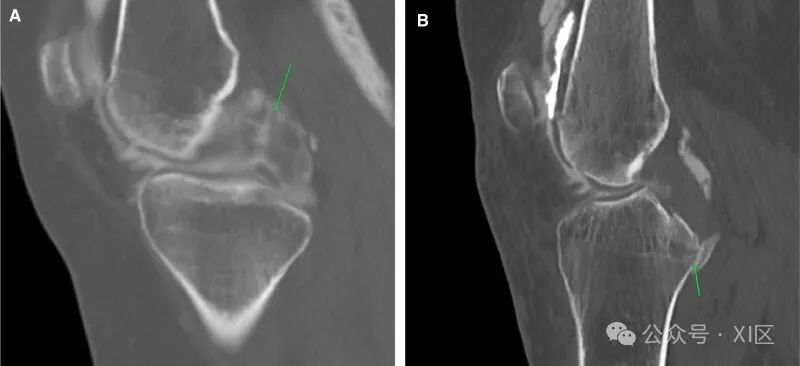

前交叉韧带(ACL)撕裂是导致内部损伤的最常见原因。如果仔细观察,预先计划的CT显示股骨外侧髁的血肿和压痕(图1)。在手术台上评估过程中可以看到带血迹的抽吸物,对比后图像显示全厚度缺损。仔细检查横断位图像至关重要,因为微小的全厚度撕裂很容易被忽视。CT关节造影提供了一个独特的优势,因为与MRI不同,多平面重建(MPR)可以在任何平面上进行,而无需增加扫描时间。CT对ACL重建膝关节特别有益(图1B),因为金属制品的原因,MRI是禁忌。必须仔细检查软组织窗图像,以便更好地解释。ACL撕脱伤通常是潜在骨折的副产品。预规划图像显示了发际骨折(图1C)。台上评估显示吸出物带血,对比后图像显示ACL和骨折线增厚。在CT关节造影检查中很难检测到部分撕裂或粘液样变性。在适当的临床环境中,前交叉韧带的体积外观、纤维的广泛分离和物质内对比可以增加诊断的可信度(图1D)。

图1 ACL撕裂:(A)关节造影后矢状位图像显示完全的ACL撕裂(箭头)。(B) 重建的前交叉韧带完全撕裂,(C)前交叉韧带撕脱(箭头)。(D) 物质内对比的粘液样变性(箭头)。后交叉韧带(PCL)损伤在外观上与ACL损伤非常相似(图2A)。PCL撕脱也与潜在的骨折和血肿有关(图2B)。